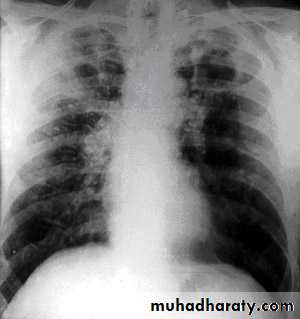

The clinical and radiological features are similar to those of coal worker's pneumoconiosis, with multiple well circumscribed 3–5-mm nodular opacities, predominantly in the mid- and upper zones

Enlargment of the hilar glands with an 'egg-shell' pattern of calcification is characterestic.

Silicosis are at increased risk of tuberculosis (silicotuberculosis), lung cancer and COPD.